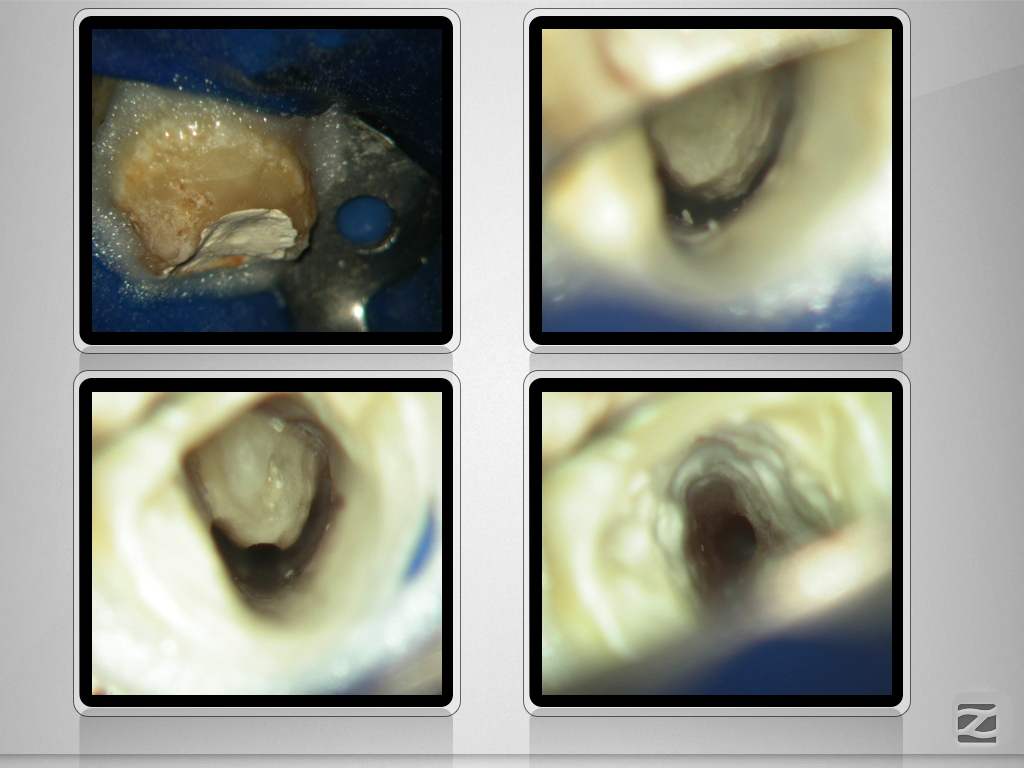

36D.007

C-shape plus Radix entomolaris